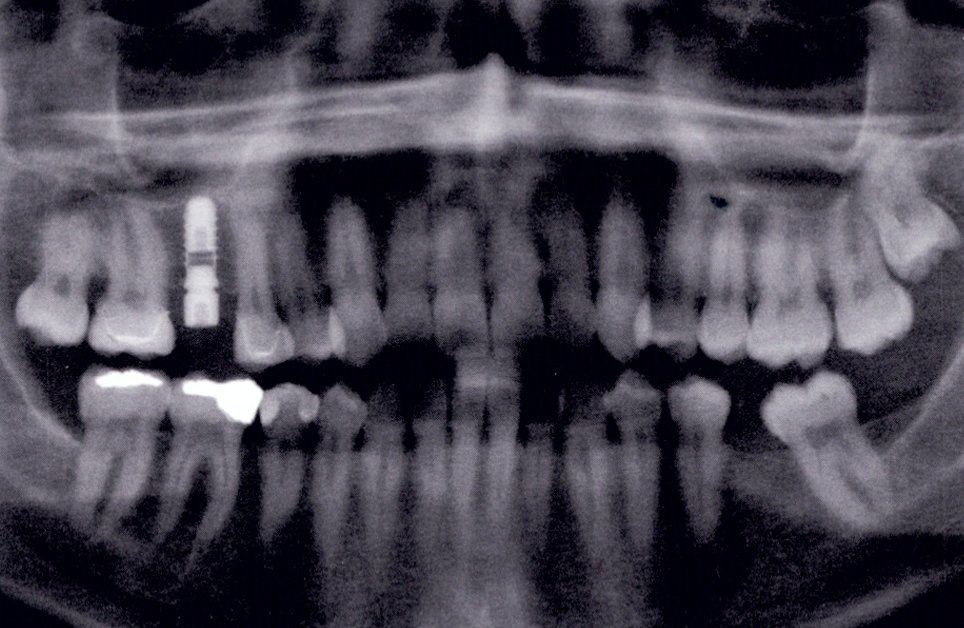

Può essere eseguita sia nell'arcata dentale superiore che nell'arcata dentale inferiore sempre che le condizione ossee lo rendano possibile, è per questo motivo importante fare un analisi radiografica dettagliata tridimensionale Conebeam.